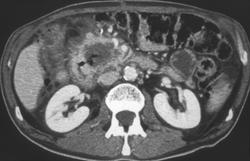

Minimum Intensity Projection and Volume Rendering of Dilated Common Duct